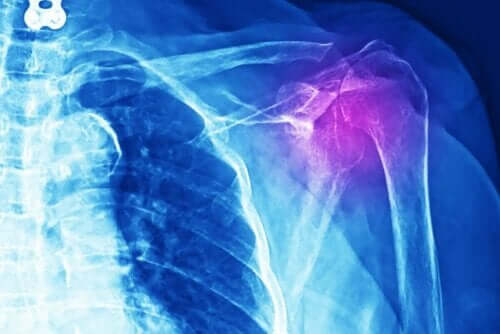

Doktorların, bu tür sakatlıkları teşhis etmek için çeşitli testler yapmaları gerekir. Röntgen, ultrason, MRG veya bilgisayarlı eksenel tomografi (BT taraması) yapmayı tercih edebilirler. Bunun yanı sıra tıbbi muayene yapmaları ve hastanın tıbbi geçmişini ayrıntılı bir şekilde incelemeleri gerekir.